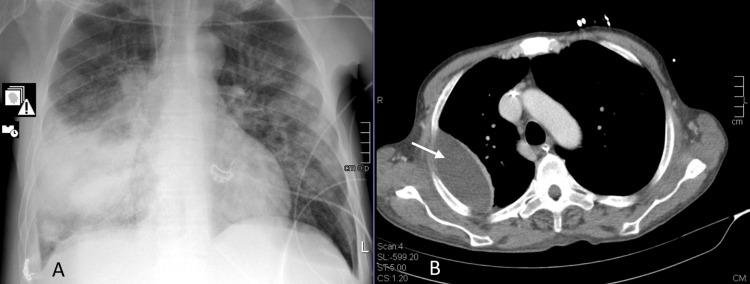

Pneumococcal infection is still a frequent disease. It can be classified as invasive when pneumococcus is isolated in a generally sterile fluid. Pneumonia is the most common infectious source of adult invasive pneumococcal disease (IPD), and several risk factors for IPD are well known. This case report presents three clinical cases of different manifestations of IPD. The two most severe cases had coinfection by SARS-CoV-2 at hospital admission.

肺炎球菌感染仍然是一种常见疾病。当在通常无菌的液体中分离出肺炎球菌时,可将其归类为侵袭性感染。肺炎是成人侵袭性肺炎球菌病(IPD)最常见的感染源,并且IPD的几种危险因素已为人熟知。本病例报告展示了IPD不同表现形式的三例临床病例。其中两例最严重的病例在入院时合并感染了SARS-CoV-2。